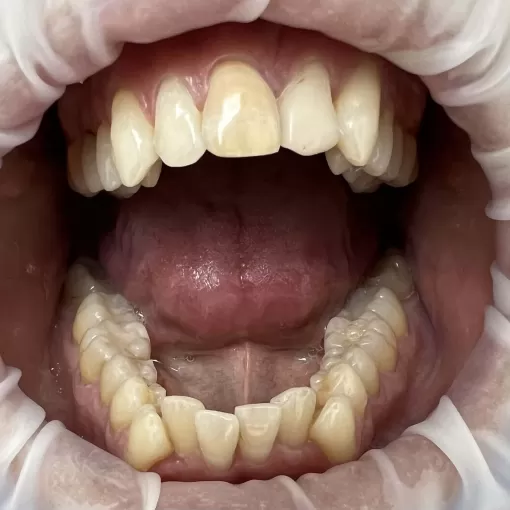

жалобы на скученность зубов на нижней челюсти и вестибулярное положение клыка на верхней челюсти справа

Пациентка обратилась с жалобы на скученность зубов на нижней челюсти и вестибулярное положение клыка на верхней челюсти справа.